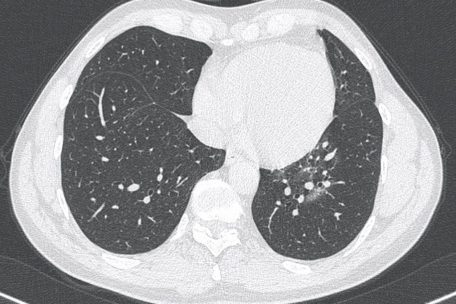

Das dreidimensionale Schnittbild aus dem Körperinneren, das der CT-Scanner liefert, ist bei vielen Krankheitsbildern enorm hilfreich – so auch bei der Bewertung einer Covid-19 -Erkrankung: So kann etwa genau erkannt werden, an welchen Stellen das Virus die Lunge möglicherweise bereits befallen hat. Dort kommt es zu Ansammlungen zäher Flüssigkeit in den Lungenbläschen („Milchglastrübungen“). Im schlimmsten Fall verfestigt sich das Lungengewebe und wird irreparabel geschädigt. Kann das nicht aufgehalten werden, droht der Tod. Durch das CT kann das Vorliegen von Covid-19 „bereits sehr früh im Laufe der Erkrankung“ erkannt werden, heißt es in den medizinischen Leitlinien.

„In der schnellen Notfalldiagnostik bei Patienten mit akuten respiratorischen Symptomen hat sich bei einer zunehmenden Auslastung der Kapazitäten eine schnelle Abklärung einer Covid-19-Erkrankung durch ein Thorax-CT als nützlich erwiesen“, stellt außerdem die E-Health-Webseite Digithurst.Net fest. Dies gelte „insbesondere, wenn man bei einer hohen Zahl an Neuaufnahmen Patientengruppen mit und ohne Covid-19 konsequent voneinander trennen möchte.“